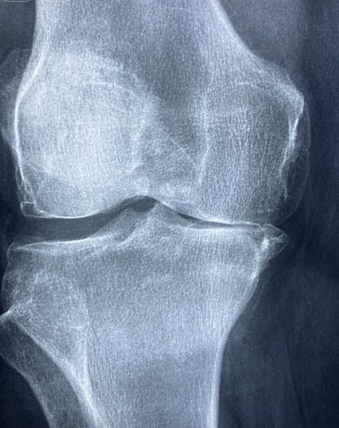

영상 검사: X-ray나 MRI를 통해 슬개골과 주변 구조를 확인하여 슬개골연골연화증 여부를 판단합니다.